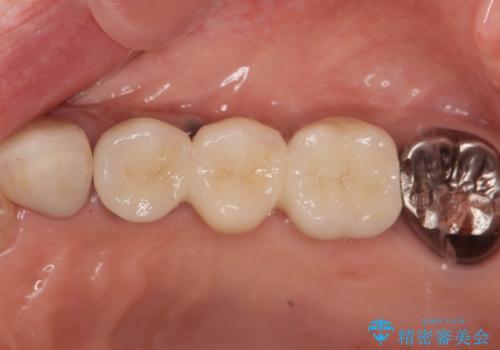

インプラント2本で3本分の咬合機能を回復することができました。(インプラントブリッジ治療)